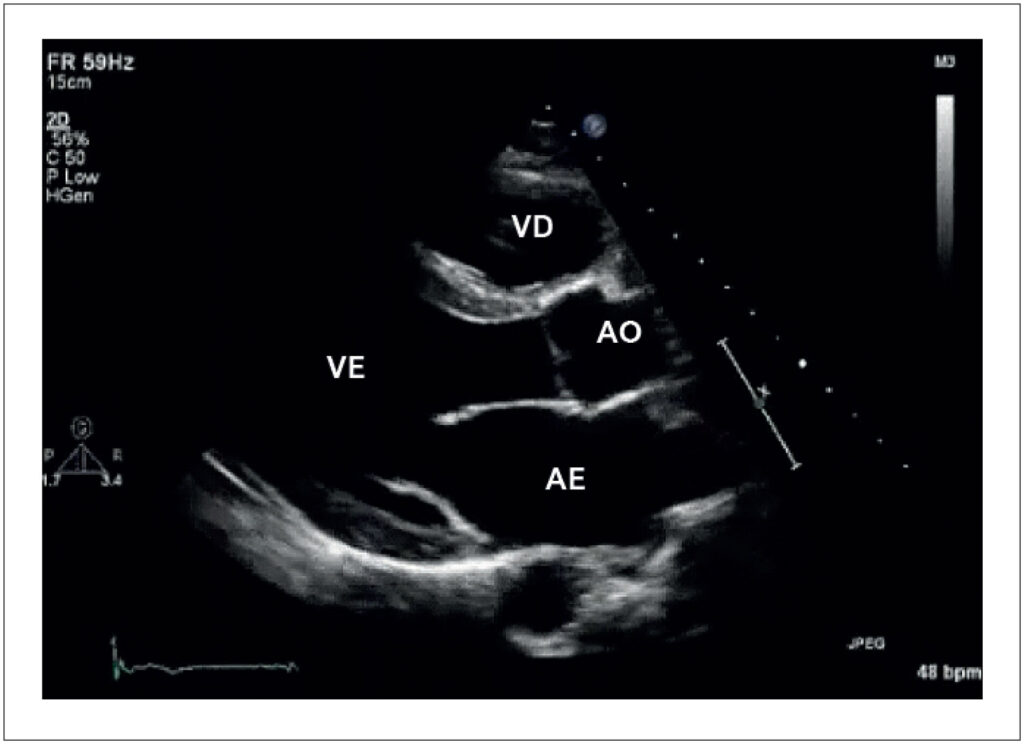

A prática regular de esportes pode induzir adaptações no coração, sendo essa condição comumente chamada de “coração de atleta”. As alterações observadas incluem dilatação das câmaras cardíacas, aumento da espessura miocárdica, melhora do enchimento ventricular, aumento da trabeculação do ventrículo esquerdo (VE), dilatação da veia cava inferior, entre outras. Essas alterações também podem ser observadas em algumas doenças cardíacas, como cardiomiopatia (CMP) dilatada, hipertrófica e outras. Dessa forma, os exames de imagem cardíaca são fundamentais na identificação dessas alterações e na diferenciação entre o “coração de atleta” e uma possível cardiopatia.